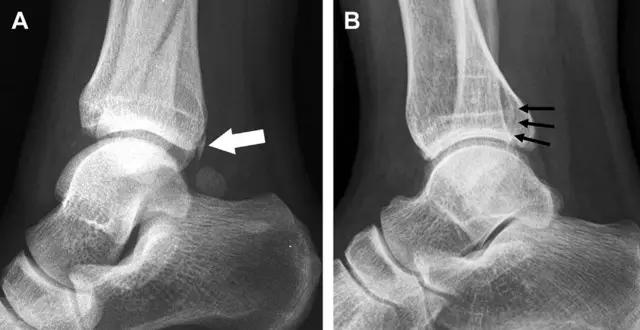

19 距骨后突骨折

距骨后突有内侧结节和外侧结节,距骨后突内侧结节撕脱性骨折常发生在背屈内旋的*力暴**作用下。严重跖屈时,胫骨后缘和跟骨挤压距骨后突外侧结节呈楔形,易发生粉碎性骨折。这些骨折细微且需与三角骨鉴别。侧位片观察距骨后突骨折最佳,常规拍片很难发现,当高度怀疑这种骨折又没法做 CT 时,建议加做多个角度的外旋斜位片(图 5)。

图 5 距骨后突骨折。侧位片(A)和 MRI 矢状位 T1 加权像(B)均示后外侧突的简单骨折(箭头),再次阅片时才发现 X 线片上的骨折;侧位片(C)和 CT 横断面图像示后内侧突的粉碎型骨折(箭头)